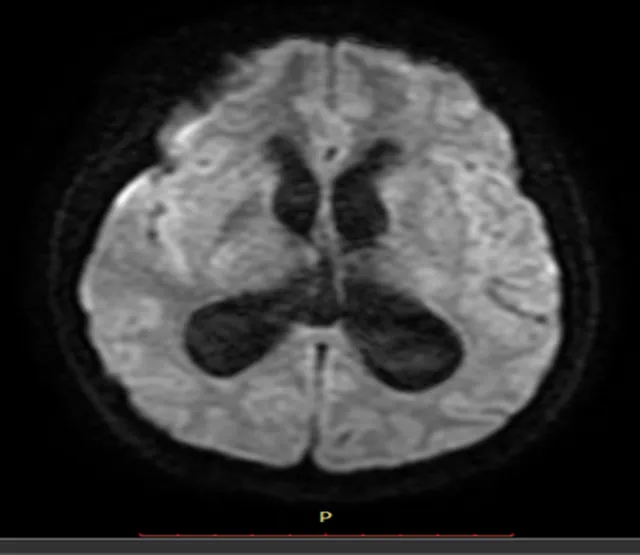

Resonancia Magnética Cerebral Simple

Hallazgo en RNM Cerebral

A nivel de brazo anterior de capsula interna derecha se observa pequeña área con cambios de intensidad de la señal de comportamiento magnético isointenso en T1 con respecto a la sustancia gris, e hiperintenso en T2 con restricción hídrica en difusión, mide 6.0 mm x 5.0 mm en sus mayores ejes sin repercusión sobre estructuras adyacentes.

Se observa dilatación simétrica en ventrículos laterales así como de tercer y cuarto ventrículo, este último provocando desplazamiento de mesencéfalo y parénquima cerebeloso en sentido anterior y posterior respectivamente, asociada a hiperintensidad moderada de la sustancia blanca periventricular en secuencia FLAIR en relación con edema intersticial.